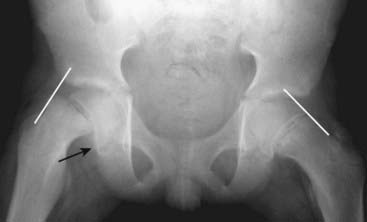

Figure 22-11 Avulsion fractures, ASIS and lesser trochanter.

Avulsion fractures are common fractures in which the avulsed fragment is pulled from its parent bone by contraction of a tendon or ligament. Although avulsion fractures can occur at any age, they are particularly common in younger individuals who engage in athletic endeavors. There is an avulsion of the anterior superior iliac spine (ASIS) (solid white arrow), which is the site of the insertion of the sartorius muscle. There is also an avulsion of a portion of the lesser trochanter, on which the iliopsoas muscle inserts (dotted white arrow). The patient had participated in track and field events a week prior to this radiograph.

Figure 22-12 Healing avulsion fracture of ischial tuberosity.

Avulsion fractures of the pelvis occur in anatomically predictable locations (tendons insert on bones in known locations) and they are typically small fragments. Sometimes they heal with such exuberant callus formation that they can be mistaken for a bone tumor. This is a healing fracture (solid black arrows) of the ischial tuberosity originally caused by contraction of the hamstring muscles. There is a great deal of external callus present (solid white arrow).